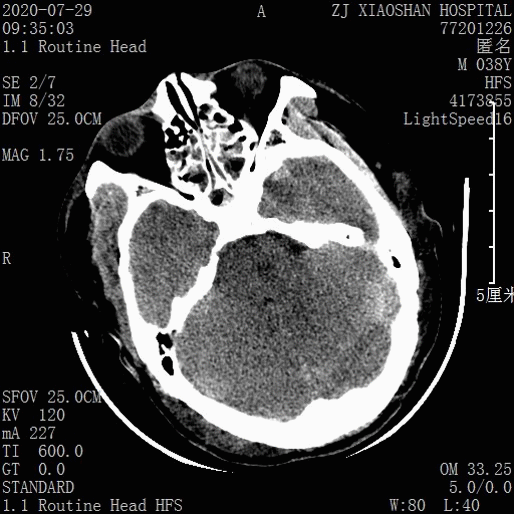

术后第5天CT:

2、术后左额叶血肿增大、脑组织水肿明显,是否需“血肿清除及去骨瓣减压”,手术指征如何把握?